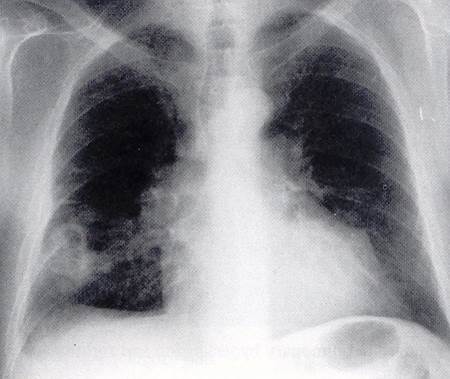

Chest X-ray findings in PE

–> pleural effusion, atelectasis, pulmonary infiltrates, mild elevation of the hemidiaphragm and frank pulmonary infarction may occur